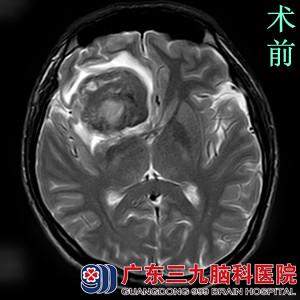

患者在家人的陪伴下找到广东三九脑科医院综合神经外科的鲁明主任,行头颅MRI检查提示右侧额叶占位性病变,考虑为血肿形成(急性期与亚急性早期混合),经SWI检查提示病变周围脑组织水肿呈高信号影,周边未见明确畸形静脉血管影。结合病史,鲁明主任诊断小周是颅内隐匿性血管畸形——海绵状血管瘤。

完善相关检查后,由鲁明主任主刀,在全麻下行右侧额叶海绵状血管瘤切除术+血肿清除术。术中导航定位右侧额叶病变,显微镜下见血肿,予吸引器吸出凝血块,见右侧额叶内侧病变,予显微镜下全切除,手术顺利结束。术后经过专科治疗护理,两周后康复出院。术后病理结果:海绵状血管瘤。